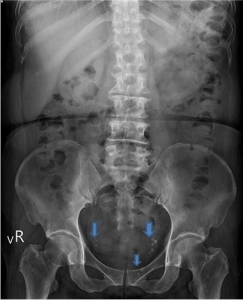

右圖:花蓮慈院婦產部婦科主任兼婦科微創手術中心主任龐渂醛表示,臨床上,有些病人可以從腹部X光發現可見鈣化點(藍箭頭白點),這是慢性發炎的證據。